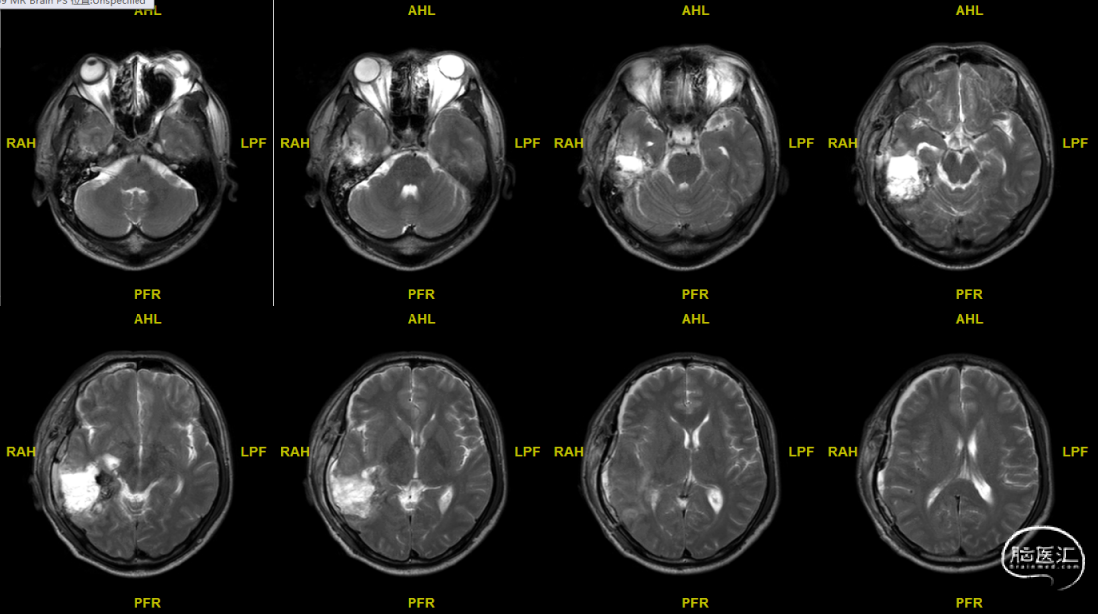

术前MRI

术后MRI